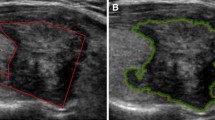

To determine which Breast Imaging Reporting and Data System (BI-RADS) descriptors for ultrasound are predictors for breast cancer using logistic regression (LR) analysis in conjunction with interobserver variability between breast radiologists, and to compare the performance of artificial neural network (ANN) and LR models in differentiation of benign and malignant breast masses. Five breast radiologists retrospectively reviewed 140 breast masses and described each lesion using BI-RADS lexicon and categorized final assessments. Interobserver agreements between the observers were measured by kappa statistics. The radiologists’ responses for BI-RADS were pooled. The data were divided randomly into train (n = 70) and test sets (n = 70). Using train set, optimal independent variables were determined by using LR analysis with forward stepwise selection. The LR and ANN models were constructed with the optimal independent variables and the biopsy results as dependent variable. Performances of the models and radiologists were evaluated on the test set using receiver-operating characteristic (ROC) analysis. Among BI-RADS descriptors, margin and boundary were determined as the predictors according to stepwise LR showing moderate interobserver agreement. Area under the ROC curves (AUC) for both of LR and ANN were 0.87 (95% CI, 0.77–0.94). AUCs for the five radiologists ranged 0.79–0.91. There was no significant difference in AUC values among the LR, ANN, and radiologists (p > 0.05). Margin and boundary were found as statistically significant predictors with good interobserver agreement. Use of the LR and ANN showed similar performance to that of the radiologists for differentiation of benign and malignant breast masses.